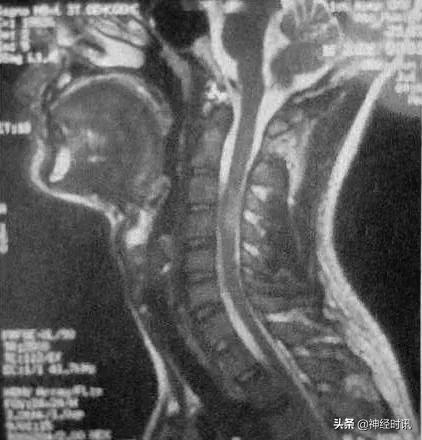

颈椎MRI(2011年10月):C2~C4可见脊髓肿胀,其内可见稍长T1,长T2信号影,无强化。

临床诊断上,除了McDonald2010年诊断标准(现已更新至McDonald2017年诊断标准)外,MRI也具有十分重要的重要。结合上述病例,该患者头部MRI中有多发的白质部分病灶,颈部MRI中可见单个椭圆形病灶,边界清楚。